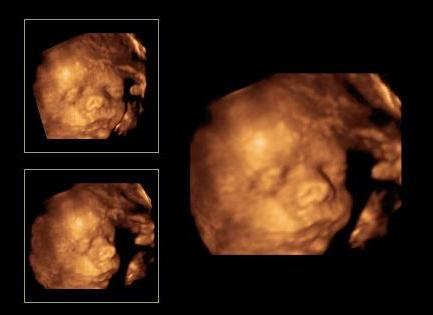

4 D-s UH-t is megjártuk hétvégén, hozok majd képeket ha sikerül. Édes volt a kisfiunk, születtek jó képek, bár néha bújt a lepénybe. :)

Kép Hamm...

Kép Kukucs...

Kép Megsimogatlak anya...

Kép Cumi...

Kép